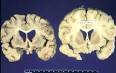

Maladie de Creutzfeldt-Jakob p dia La maladie de Creutzfeldt-Jakob (MCJ) est une d g n rescence du syst me nerveux central. Nombre de cas certains ou probables de MCJ en France, Institut de. Cellule de r f rence de la maladie de Creutzfeldt-Jacob sur le site de l APHP.

Maladie de Creutzfeldt-Jakob p dia